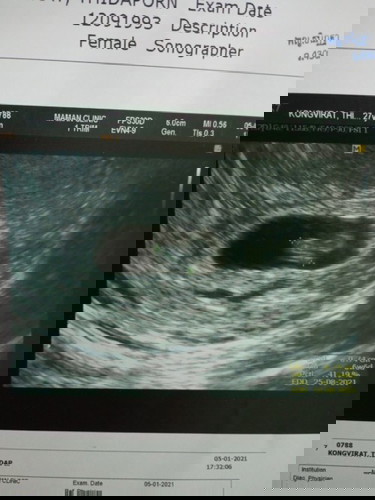

แม่ๆท่านไหนเคยเป็นไหมค่ะ ท้องที่2แล้วอายุ ครรภ์ได้แค่ 7-8 สัปดาห์ มีเลือดออกแล้วน้องหัวใจหยุดเต้น

น้องไม่อยู่แล้วค่ะ 😔😔